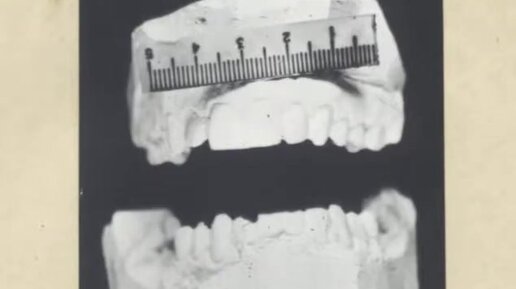

Медико-криминалистическая идентификация человека.